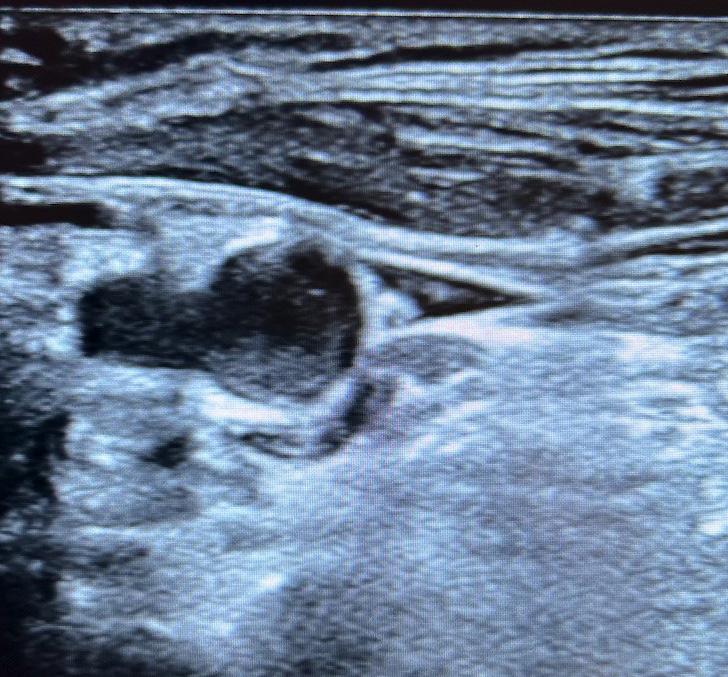

In the case covered in this article, an 85-year-old man with septic shock caused by a perforated sigmoid colon was profoundly hypovolemic and required crystalloid resuscitation and dual vasopressors. Ultrasound revealed that his internal jugular vessels were completely collapsible. Initial attempts to place the catheter were unsuccessful due to vessel collapse. The Trendelenburg position did not adequately dilate the internal jugular vein, as shown in Image 1. However, using a passive leg raise, significant dilation of the internal jugular vein was observed, enabling successful cannulation (Image 2).